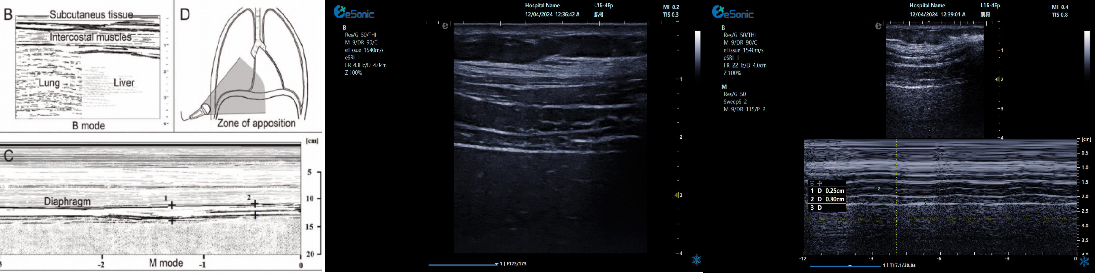

重症肺部超声

超声声像图:声束垂直胸膜线时,可见多条A线与胸膜线平行,且等间距。

膈肌超

评估内容:膈肌移动度、膈肌厚度、增厚率。

评估意义:判断病人膈肌功能,呼吸功能,脱机前后评估等

常用检查模式:B、M

检查探头:凸阵、线阵

对超声设备要求:M型、解剖M型;测量快速准确;有专用的测量包

膈肌厚度检查

image.png

探头:高频线阵探头

部位:放置于腋前线与腋中线,7/8肋间或8/9肋间,沿肋间隙放置,观察和测量膈肌的厚度。

功能:M型超声,膈肌测量包

膈肌厚度变化

膈肌厚度测量

呼气末膈肌厚度正常值为2.0-3.5cm

膈肌活动度检查

探头:低频探头

部位:放置在腋前线或锁骨中线与肋缘交界处,启用M模式取样线垂直于膈肌,观察和测量膈肌运动幅度。

功能:M超,膈肌测量包

膈肌活动度测量